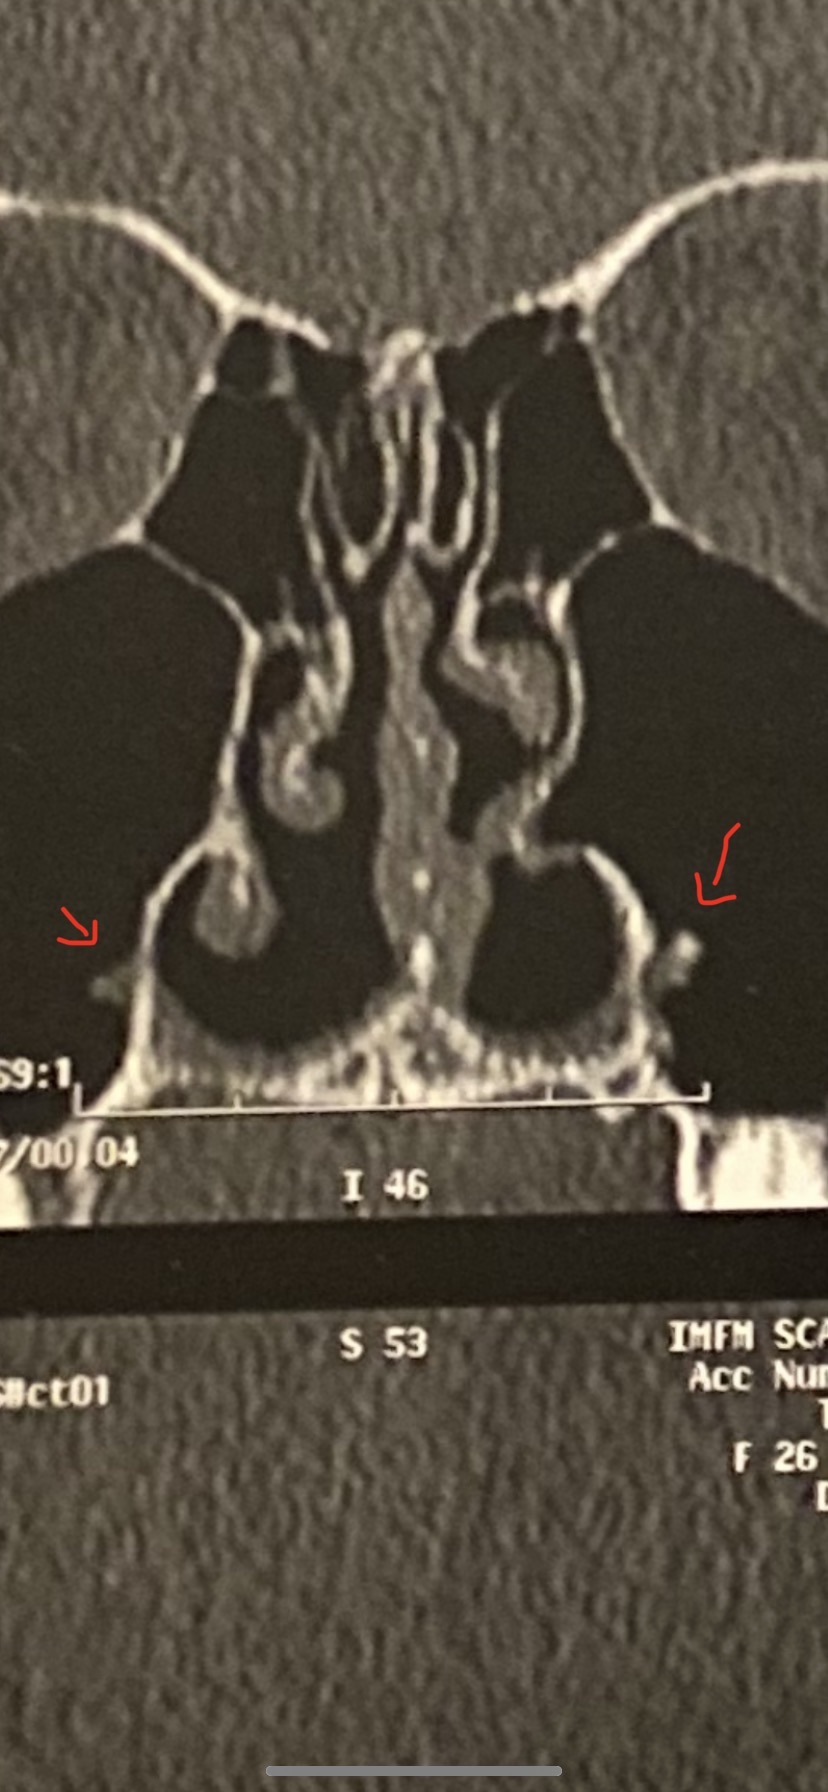

Hello Dr, I have pain in my nose after rhinoseptoplasty (a lot of grafts were placed), I want to know regarding the scan, what are the spurs pointed with a red arrow? Could it provoke pain? I also would like to know if the second image show scar tissue in my sinus or something else I know I have a synechia that I will need removed because it's causing congestion.. Thank you in advance